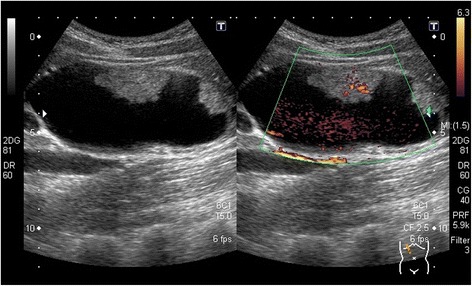

Abdominal ultrasonography revealed a cystic dilatation of the extrahepatic bile duct and two protruding tumors in the lumen of the dilated common bile duct (Fig. 1). Doppler ultrasound detected a blood flow signal within the tumor. Abdominal computed tomography (Fig. 2) demonstrated a cyst within the common bile duct measuring 7 cm in diameter and two enhanced tumors measuring 4 cm in diameter located in the inferior bile duct and middle bile duct. Magnetic resonance cholangiopancreatography (Fig. 3) clearly demonstrated a cystic dilatation of the extrahepatic bile duct (Todani’s CBD classification: type 4-A) [ref. 1]. Endoscopic retrograde cholangiopancreatography (Fig. 4) also demonstrated a cystic dilatation of the bile duct as well as the presence of two tumors. Biopsy of one of the tumors confirmed the presence of adenocarcinoma. Amylase, CA19-9, and carcinoembryonic antigen levels in the choledochal cyst were 54,722 IU/l, 230,853 U/ml, and 3.051 ng/ml, respectively.